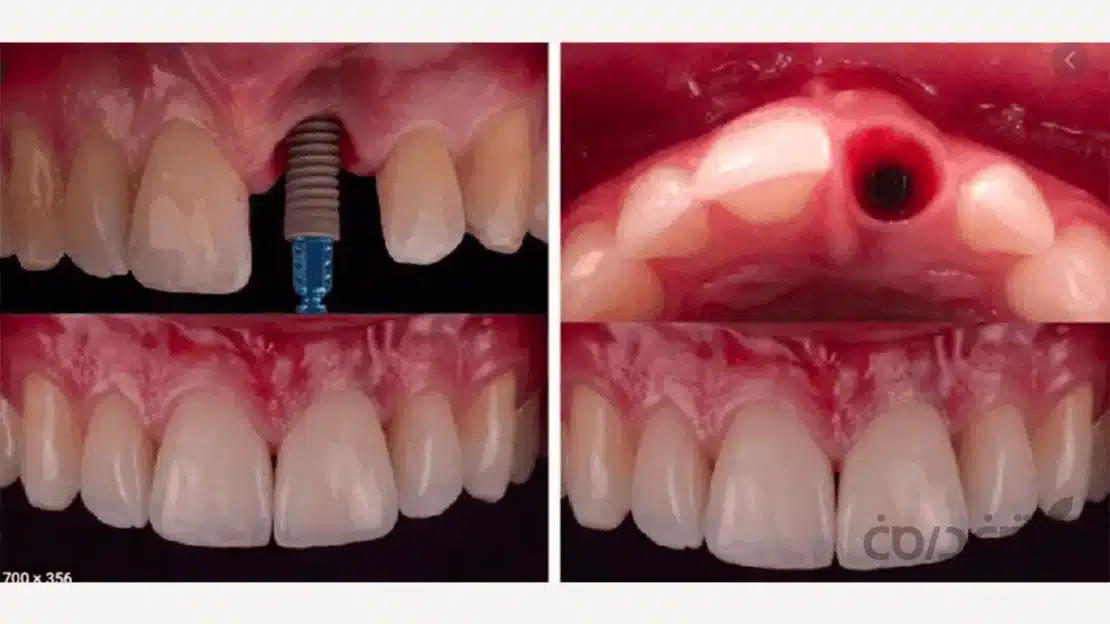

15 آذر مقالات, مقالات ایمپلنت دندان همه چیز درباره زمان بندی کاشت ایمپلنت پس از کشیدن دندان 22 آذر 1404 توسط آرتمان درمان 0 دیدگاه شاید شما یک دندانتان را از دست دادهاید یا در آستانه کشیدن آن هستید و اکنون با یک دوراهی مهم روبرو هستید. سوالی که ذهن شما را به خود م... ادامه مطلب